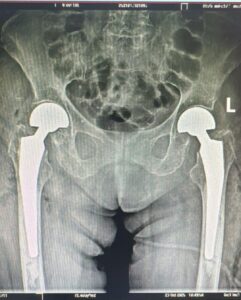

Având în vedere complexitatea cazului, pacienta a fost internată pe secția de Ortopedie pentru pregătirea intervenției chirurgicale. După o evaluare preoperatorie atentă și stabilizarea statusului general, echipa operatorie a realizat o procedură în premieră pentru județul nostru: artroplastie parțială de șold bilateral, cu proteze bipolare cimentate, efectuată în același timp operator.

Particularitatea cazului constă atât în diagnosticul rar (fractura bilaterală de col femural), cât și în realizarea unei intervenții simultane pe ambele șolduri, o procedură cu un grad ridicat de dificultate.